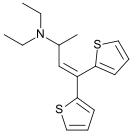

Thiambutenes

Structures